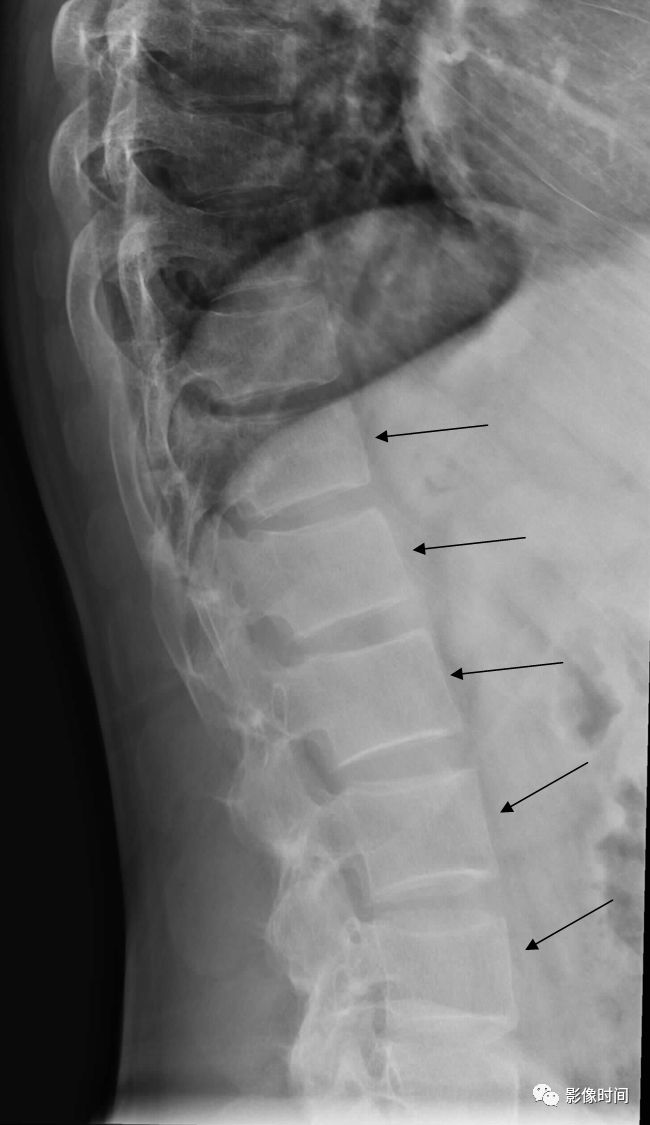

19竹节椎

竹节椎(Bamboo spine)

竹节椎是用于描述强直性脊柱炎的一个放射学特征,由于椎旁韧带广泛骨化,导致椎体融合强直,这种薄而连续的韧带骨化在正位片使得脊柱的轮廓呈现波浪起伏状,宛如具有多个竹节的一根竹竿,故而得名。

典型病例

强直性脊柱炎。腰椎正位片示腰椎韧带、小关节囊广泛骨化,骨性强直,呈典型竹节椎表现。另可见骶髂关节骨性融合。

20匕首征

匕首征,或译为短剑征(Dagger sign)

匕首征是指由于棘间韧带骨化,导致在正位 X 线片上呈现垂直的一条硬化带(白箭),形似一把短而窄的匕首而得名。此征象也主要用于描述强直性脊柱炎。

强直性脊柱炎。正位 X 线片示棘间及棘上韧带骨化形成匕首征(黄箭)。另可见双侧骶髂关节骨性融合,双髋关节间隙均匀性狭窄。

21

电车轨道征

电车轨道征(trolley-track sign)

电车轨道征是指在正位 X 线片上,强直性脊柱炎患者由于棘上及棘间韧带骨化,两侧小关节囊骨化强直,形成竖向排列的三条高密度线,类似无轨电车的轨道,故而得名。

63 岁女性,强直性脊柱炎。正位 X 线片示由于棘上及棘间韧带骨化以及关节突关节强直,呈现电车轨道征。

22亮角征

亮角征(shiny corner sign),又称 Romanus 病灶(Romanus lesion)

亮角征指的是在侧位片或者 CT、MRI 矢状位图像上,椎体的上角或者下角密度(或信号)增高(黑箭),「发亮」,故而得名。本征象主要见于血清阴性脊柱关节病(尤其是强直性脊柱炎)。在 X 线片上此征象的出现是由于于椎体角部炎症性侵蚀而导致的反应性骨质硬化。在磁共振上,活动性疾病表现为 T1WI 低,T2WI 压脂高信号,疾病进程后期则因为脂肪骨髓变性而呈现 T1WI、T2WI 双高信号。

病例 1,53 岁男性,强直性脊柱炎。侧位 X 线片示部分椎体前上角密度增高,呈亮角征(黑箭)。

病例 2,男性,38 岁。强直性脊柱炎。A. 矢状位 T1WI 示胸腰段多发椎体角部信号增高(白箭),呈亮角征;B.STIR 序列亦呈稍高信号(白箭, 提示有活动性炎症)。

引用自:https://radiopaedia.org/articles/shiny-corner-sign-ankylosing-spondylitis

23方形椎体/方椎

方形椎体/方椎(Squared vertebral body)

侧位观,A. 椎体前缘正常轮廓是略向内凹陷的;B. 在某些疾病时,椎体前缘失去内凹的轮廓(白箭),变得平直,即称为方椎。本征象多用于描述血清阴性脊柱关节病。

男性,33 岁。强直性脊柱炎。侧位片示胸腰段多个椎体前缘失去凹陷轮廓,呈方椎改变。